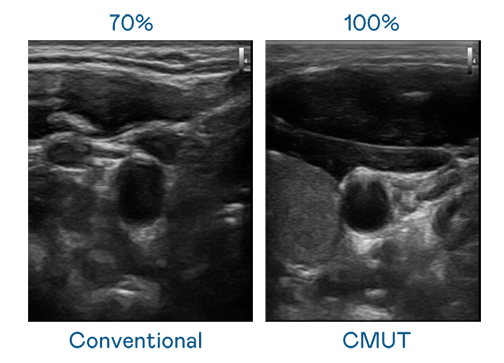

CMUT 技術是一種用電容式微機電元件來產生超音波訊號的技術。與傳統 PZT 壓電式技術相比,CMUT 頻寬增加 30%,更寬頻的超音波訊號讓影像解析度大幅提升,是實現高影像品質醫療超音波掃描、促進精準醫療發展的關鍵技術。

大頻寬帶來超清晰影像

超音波影像的解析度高低,首先取決於探頭能發出的訊號頻寬。hth华体育官网网页版 CMUT 可提供高清晰的超音波訊號,提供高頻寬、高靈敏度、影像紋理細節更高的超音波影像,協助醫護人員縮短影像判讀時間及利用精準的醫療影像進行診斷。